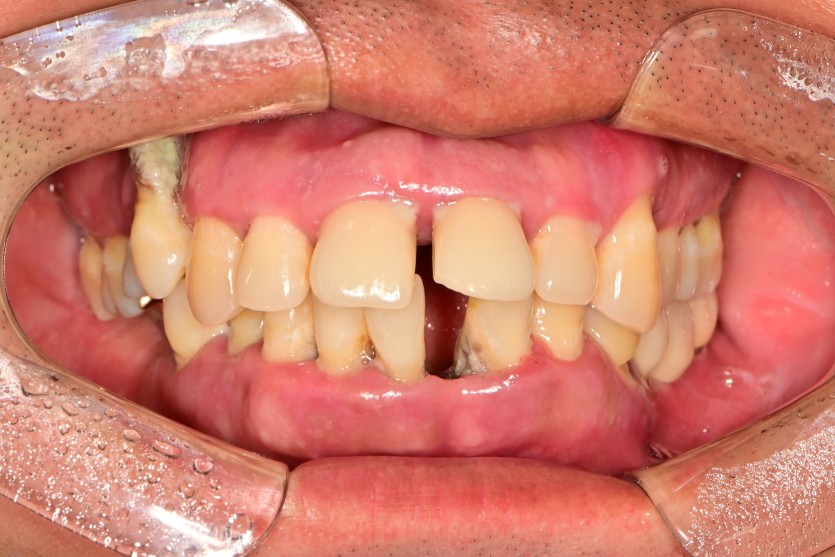

만 41세 전체 임플란트 증례

전체 임플란트 증례입니다.